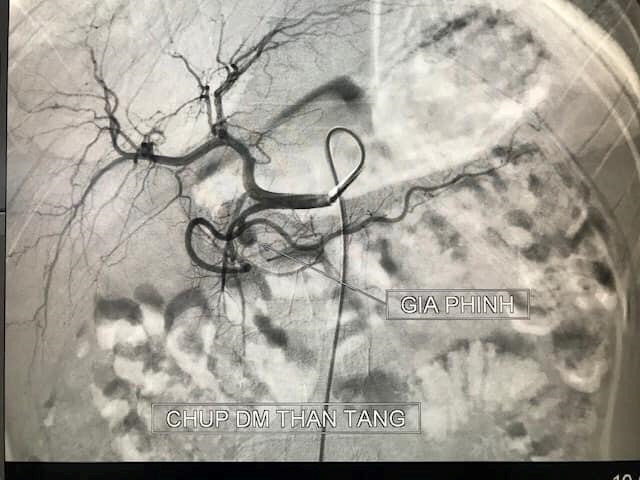

Bác sĩ Lê Thanh Dũng, Phó trưởng khoa Chẩn đoán hình ảnh, Bệnh viện Hữu nghị Việt Đức cho biết, bệnh nhi nhập viện trong tình trạng nôn ra máu liên tục không tự cầm. Kết quả chụp cắt lớp vi tính cho thấy bệnh nhi có ổ giả phình lớn động mạch vị tá tràng.

Bệnh nhi được bác sĩ can thiệp cấp cứu ngay. Sau 20 phút can thiệp, ổ giả phình đã được loại bỏ hoàn toàn. Bệnh nhi hết nôn ra máu, huyết động ổn, chuyển về khoa Nhi tiếp tục điều trị tình trạng viêm tụy cấp.

| Hình ảnh ổ giả phình lớn động mạch vị tá tràng ở bệnh nhân. |

Bệnh có thể để lại những biến chứng vô cùng nguy hiểm trong đó có tổn thương mạch máu dẫn đến ổ giả phình động mạch. Những ổ giả phình mạch do men tụy phá vỡ cấu trục mạch máu bình thường. Chúng có thể vỡ gây chảy máu ồ ạt, thậm chí đe dọa tính mạng chỉ trong vài giây.